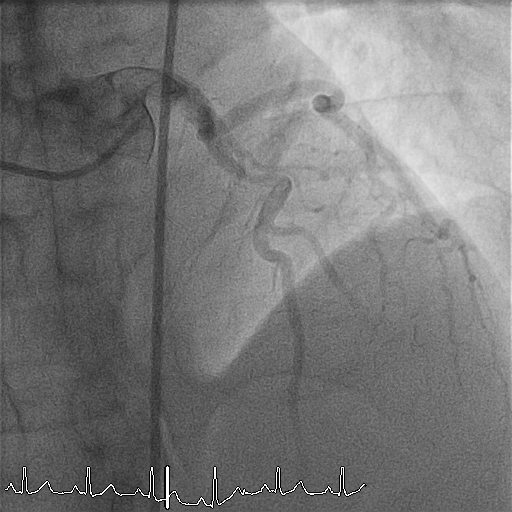

The patient arrived intubated with BP 110/62 mmHg and pulse 60/min. Echocardiography showed an LVEF of 30% with severe anterior wall hypokinesia. Coronary angiography revealed a right-dominant system with normal LMCA, LCX, and RCA (TIMI 3 flow). The proximal LAD demonstrated a subtotal thrombotic occlusion (95–99%) with a large thrombus burden and TIMI 1 flow.

The patient arrived intubated and hemodynamically stable. Right femoral artery access was obtained with a 7 Fr sheath. Diagnostic angiography confirmed subtotal thrombotic occlusion of the proximal LAD with TIMI 1 flow and a large thrombus burden. PCI was initiated using a 7 Fr EBU 3.5 guiding catheter and a Sion guidewire. An ELIMINATE 7 Fr aspiration catheter was advanced, and multiple aspiration passes were performed, but significant residual thrombus persisted with high risk of no-reflow.